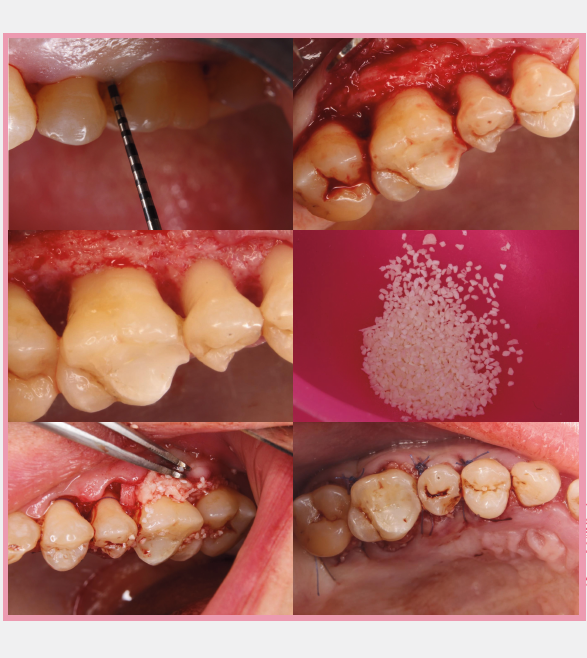

إعادة تكوين الأنسجة الموجهة

تقنية متقدمة لإعادة بناء العظام والأنسجة الداعمة للأسنان باستخدام أغشية ومواد بيولوجية متطورة

علاج انحسار اللثة

علاج متخصص لانحسار اللثة وإعادة بناء الأنسجة اللثوية لحماية جذور الأسنان وتحسين المظهر الجمالي